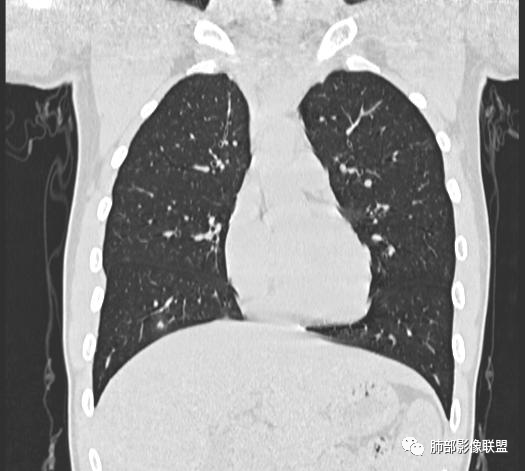

男,19岁

主  诉:发热、全身皮疹2天。

现病史:患者源于2天前受凉后出现发热,最高体温为38.5℃,且颜面部出现少量皮疹,无鼻塞、流涕、咳嗽、咳痰,未在意而未作特殊处理,次日全身皮疹逐渐增多至全身,伴轻度瘙痒,在当地卫生所给予抗病毒、抗感染治疗(具体用药不详)体温有所下降,但皮疹无明显消退,无腹痛、头痛,食欲无明显减退,为进一步诊治,遂于今日急来我院求治,患者目前精神尚可,体力正常,食欲正常,睡眠正常,体重无明显变化,大便正常,排尿正常。

小强:青年,发热,皮疹;双肺散在结节,周围磨玻璃,点晕征,疱疹病毒感染,鉴别荚膜组织胞浆菌,结核。 大雄:青年,急性起病,发热伴全身皮疹2天,抗病毒治疗体温有下降。双肺随机分布大小不等类圆结节,“点晕征”。考虑水痘-疱疹病毒(VZV)血播询问接触史,查体皮疹分布以及形态基本可诊断。 王开金江津中心医院呼吸科:青年男性,起病急,病程短,以发热,皮疹为首发症状,感染指标以单核细胞升高为主,胸部ct双肺多发结界,周围有晕,点晕表现,随机分布,同意於老师意见,水痘疱疹病毒血流感染累及肺。 王秀仙:双肺多发大小不等结节,周围有晕,边缘模糊,呈点晕征表现。青年,急性起病,发热伴全身皮疹2天,抗病毒治疗体温有下降。考虑疱疹病毒。鉴别荚膜组织胞浆菌。 傅昌瑜:19岁男性,发热、全身皮疹2天,单核细胞增高,双肺多发结节,结节边缘见边界不清磨玻璃影。点晕征+发热、全身皮疹+单核细胞增高——考虑水痘-带状疱疹病毒肺炎。 一切∮随缘:年轻男性,发热,皮疹两天,实验室,CRP,PCT增高,影像:双肺多发散在磨玻璃结节,边界欠清,大小不等,呈点晕征改变,以血管束周围分布为主,局部血管束略增粗,其它无明显改变,考虑:1:病毒性肺炎(水痘疱疹病毒?不知道皮肤有无改变)2:真菌(组织胞浆菌,血管侵袭性肺曲霉)3:GPA4:寄生虫(实验室没有看到嗜酸细胞增高) 赵山河:双肺散在结节,周围有晕,边缘模糊,呈点晕征表现。青年,急性起病,发热伴全身皮疹2天,抗病毒治疗体温有下降。考虑水痘—疱疹病毒感染。洪桥爱:青年男性,发热、皮疹2天,伴瘙痒,皮疹于面部首发,之后进展至全身,虽然没有对皮疹进行描述,但是从出疹时间及皮疹进展情况,伴瘙痒,应该就是个水痘患者;CT提示双肺随机分布结节影,部分结节伴有边界不清晕征,考虑水痘血播肺。 刘强:年轻男性,急性起病,皮疹,发热,抗感染治疗体温下降,说明有效。影像表现为散在点晕征,感染类疾病谱(疱疹病毒,真菌,结核),结合年龄,皮肤皮疹,考虑水痘-疱疹病毒性肺炎。 小兜:男性,19岁,发热皮疹两天,颜面部至全身,CRP,降钙素及单核增高。CT示双肺散在小结节,周围伴磨玻璃影,点晕征,考虑为水痘-带状疱疹病毒(varicella-zoster virus,VZV)肺炎 必有路:青年,皮疹+发热+“点晕征”→水痘-疱疹病毒(VZV) 许慧良:青年男性患者,发热、皮疹2天,体温最高38.5℃,第3天皮疹扩展至全身,伴瘙痒,胸部CT:双肺多发随机分布的小结节,结节周边见边界模糊的晕征,考虑水痘病毒感染流心明智:男,19,急性起病,发热伴全身皮疹2天。出疹顺序头→全身,抗病毒有效。胸部CT:两肺多发大小不等类圆形实性小结节影,随机分布,结节周围环绕GGO,边界模糊,呈点晕征。出疹特点是关键,未提示。考虑:血播病毒性肺炎,水痘-疱疹病毒?麻疹?鉴别荚膜组织胞浆菌、TB、血管炎、寄生虫等。 浪迹天涯:病灶多为5-10mm大小结节,结节周围可见磨玻璃样的晕环,常多发,可分布于肺内任何区域,考虑水痘—带状疱疹病肺炎如果短时间内有新的一个区域浸润,更加能说明,